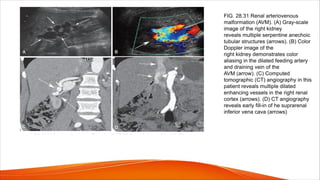

FIG. 28.31 Renal arteriovenous

malformation (AVM). (A) Gray-scale

image of the right kidney

reveals multiple serpentine anechoic

tubular structures (arrows). (B) Color

Doppler image of the

right kidney demonstrates color

aliasing in the dilated feeding artery

and draining vein of the

AVM (arrow). (C) Computed

tomographic (CT) angiography in this

patient reveals multiple dilated

enhancing vessels in the right renal

cortex (arrows). (D) CT angiography

reveals early fill-in of he suprarenal

inferior vena cava (arrows)

• When the AVF is large, high volume venous flow is observed and is

indicated by elevated Doppler velocity measurements.

• The fistula itself is typically not visualized because the communication is

small, and the affected vessel is obscured by the surrounding bruit artifact.

• The diagnosis can be made by detection of high-velocity, low-resistance

flow within the feeding artery and pulsatile flow within the affected vein

(arterialization of the venous flow)